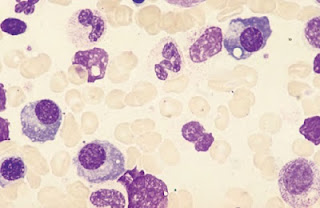

Esfregaço de sangue periférico com pancitopenia

A anemia é geralmente normocítica, com neutropenia e trombocitopenia. Leucocitose é frequente devido à presença em circulação das células leucémicas, mas pode haver leucopenia, ou leucócitos em número normal, com poucas células circulantes imaturas.